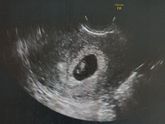

5 октября 2018 22:52 Обязательно ли перед 1 скринингом стать на учёт? И ещё, кто в Воронеже в Медэксперте на Димитрова делал скрининг 1? Анализы входят в стоимость? Или их сдавать в больнице где на учёт становишься?

1 октября 2018 19:21 Как у вас состояние на таком же сроке? Я замучалась от чувства постоянной тошноты... ком в горле. А сейчас ещё в добавок весь вечер тянет низ живота... жесть